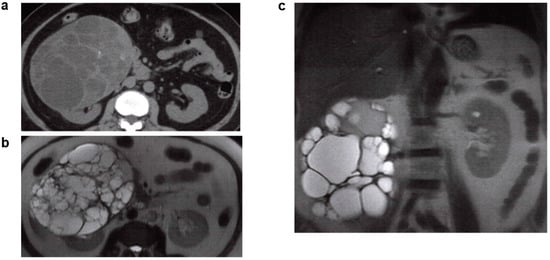

2.5. Unilateral Renal Cystic Disease (URCD)

- Levine, E.; Huntrakoon, M. Unilateral renal cystic disease: CT findings. J. Comput. Assist. Tomogr. 1989, 13, 273–276. [Google Scholar] [CrossRef] [PubMed]

- Middlebrook, P.F.; Nizalik, E.; Schillinger, J.F. Unilateral renal cystic disease: A case presentation. J. Urol. 1992, 148, 1221–1223. [Google Scholar] [CrossRef]

- Punia, R.P.; Mohan, H.; Bal, A.; Bansal, V.K. Unilateral and segmental cystic disease of the kidney. Int. J. Urol. 2005, 12, 308–310. [Google Scholar] [CrossRef]

- Hwang, D.Y.; Ahn, C.; Lee, J.G.; Kim, S.H.; Oh, H.Y.; Kim, Y.Y.; Lee, E.S.; Han, J.S.; Kim, S.; Lee, J.S. Unilateral renal cystic disease in adults. Nephrol. Dial. Transplant. 1999, 14, 1999–2003. [Google Scholar] [CrossRef] [PubMed]

- Poster, D.; Kistler, A.D.; Krauer, F.; Blumenfeld, J.D.; Rennert, H.; Weishaupt, D.; Wüthrich, R.P.; Serra, A.L. Kidney function and volume progression in unilateral autosomal dominant polycystic kidney disease with contralateral renal agenesis or hypoplasia: A case series. Am. J. Kidney Dis. 2009, 54, 450–458. [Google Scholar] [CrossRef] [PubMed]

- Porch, P.; Noe, H.N.; Stapleton, F.B. Unilateral presentation of adult-type polycystic kidney disease in children. J. Urol. 1986, 135, 744–746. [Google Scholar] [CrossRef]

| URCD | Unknown | Unilateral renal cysts resembling ADPKD in imaging. No family history of PKD, no progress to ESKD, and no complications such as hepatic cysts or cerebral aneurysm. | ||